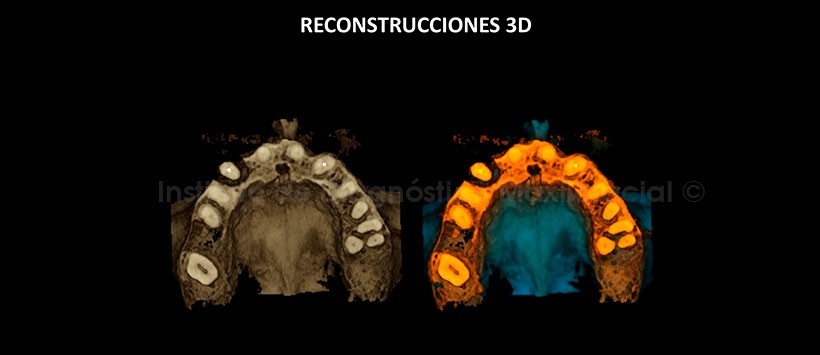

En las reconstrucciones 3D se observan la pérdida de la tabla ósea vestibular y la perdida de soporte óseo periradicular (Figura 6 y 7).